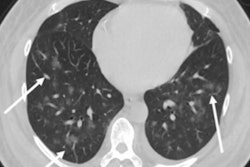

"The results of this study show a reduction of 61% in the total number of abdominal CT scans performed in patients with signs of appendicitis [during the pandemic period, and those] diagnosed with appendicitis by CT are presenting at later stages with greater disease severity," the group wrote.

Romero's group compared differences in the clinical presentation of acute appendicitis and CT findings related to these cases between the nonpandemic period before COVID-19 (March to May, 2019) and the acute COVID-19 pandemic period (March to May, 2020). The researchers evaluated the number of appendicitis cases diagnosed on CT and their level of severity. There were 141 cases in nonpandemic period and 55 in the pandemic period.

The group found that the proportion of acute appendicitis diagnosed on abdominal CT was higher in the acute pandemic period compared with the nonpandemic period, at 45.5% versus 29.8% (p = 0.038). Appendicitis cases were also more severe during the pandemic period, compared with the nonpandemic period, at 92% versus 57.1% (p = 0.003).

"During the acute pandemic period, fewer patients presented to the emergency room with suspected appendicitis, and those who did have appendicitis had more severe ... disease," the authors concluded.